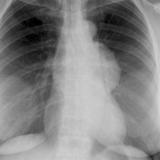

Case 9 Thymoma PA

Date: 04/04/2010

Views: 3252